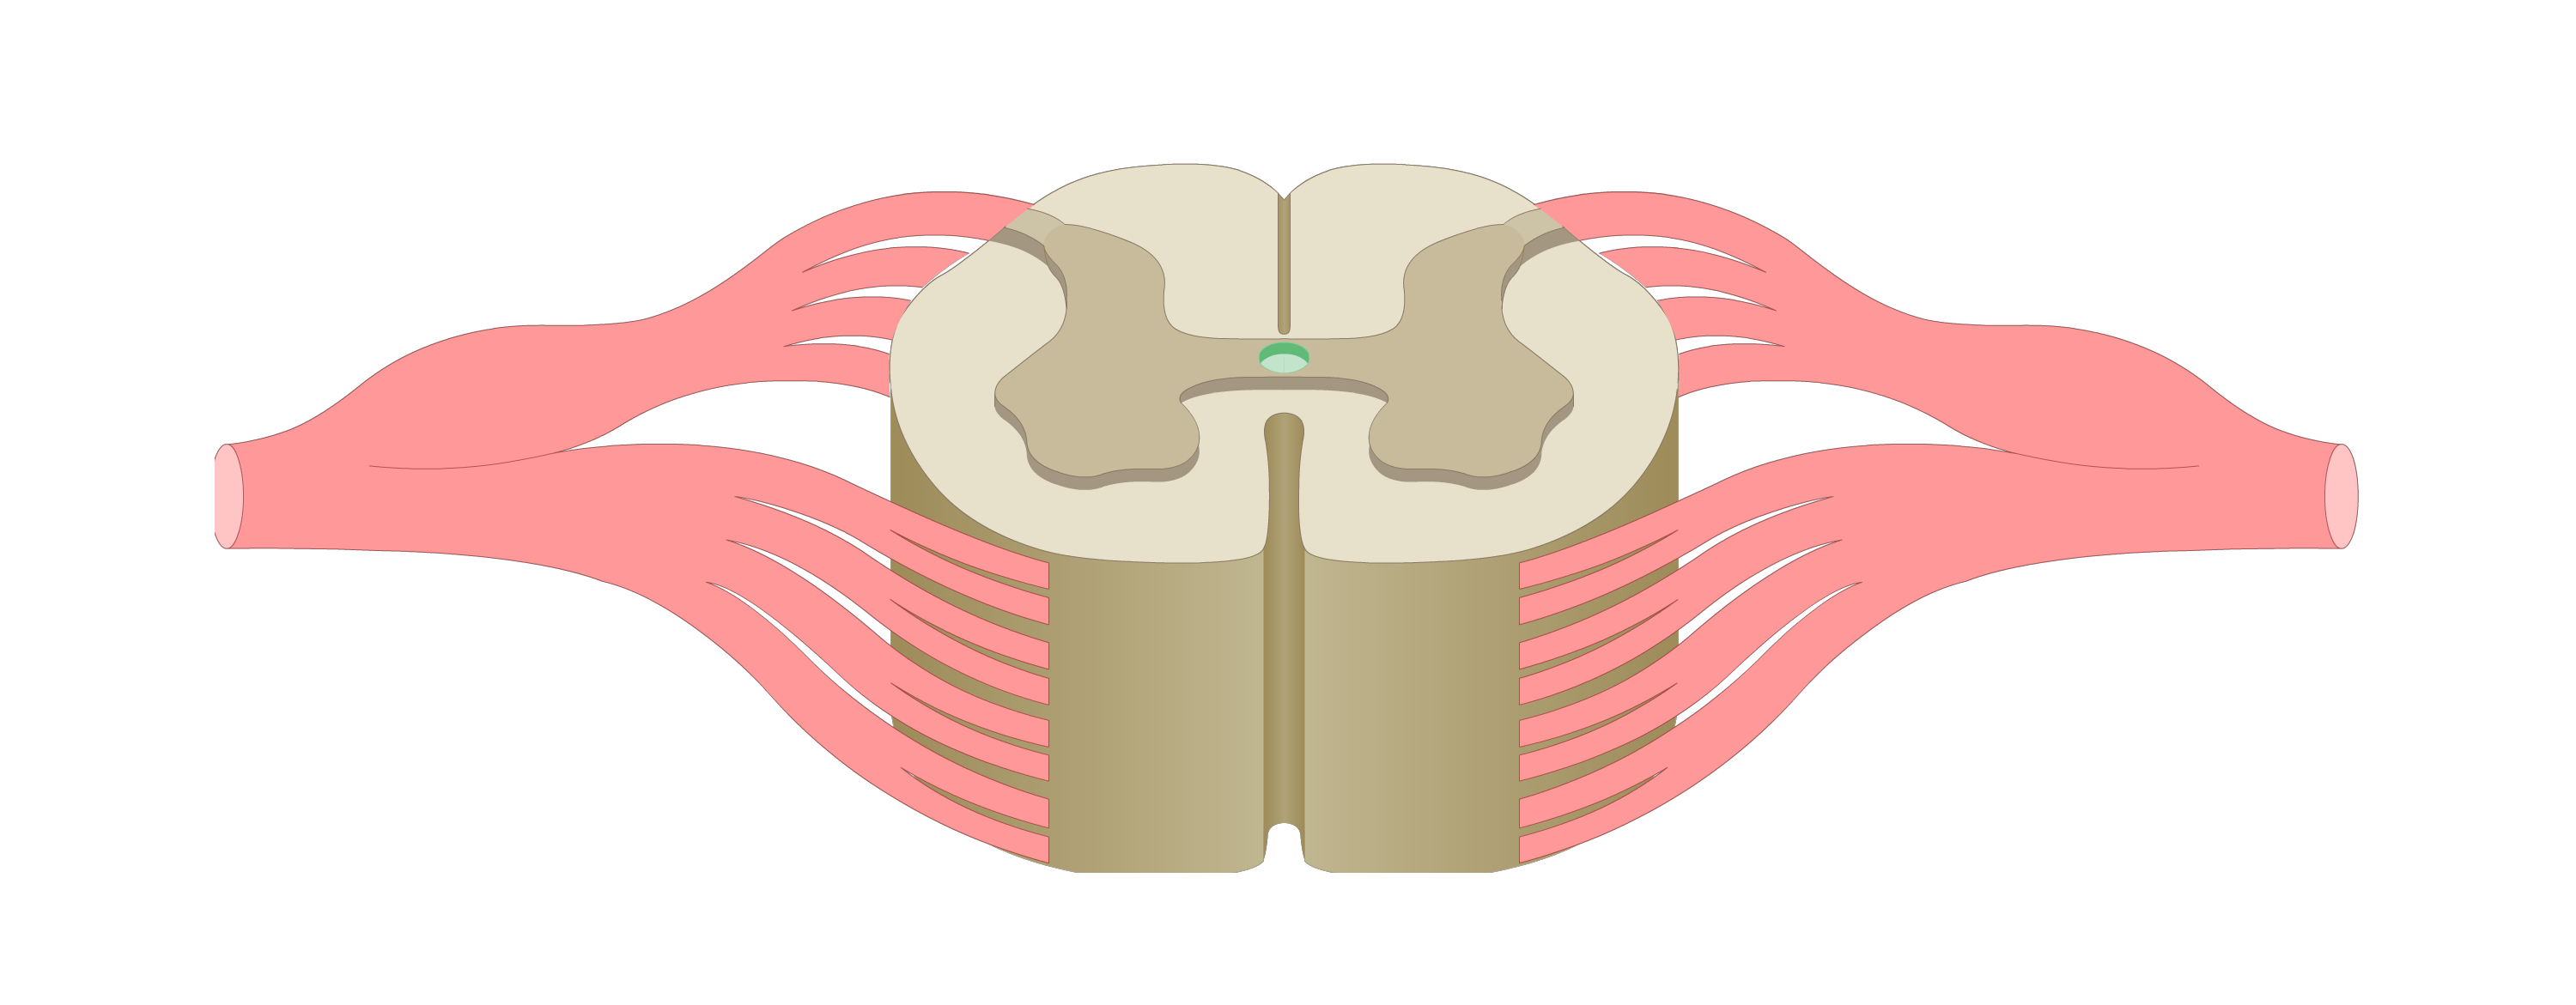

motor tracts

sensory tracts

dorsal root ganglion

dorsal horn

lateral horn

ventral horn

dorsal funiculus

lateral funiculus

ventral funiculus

central canal

ventral median fissure

dorsal median sulcus